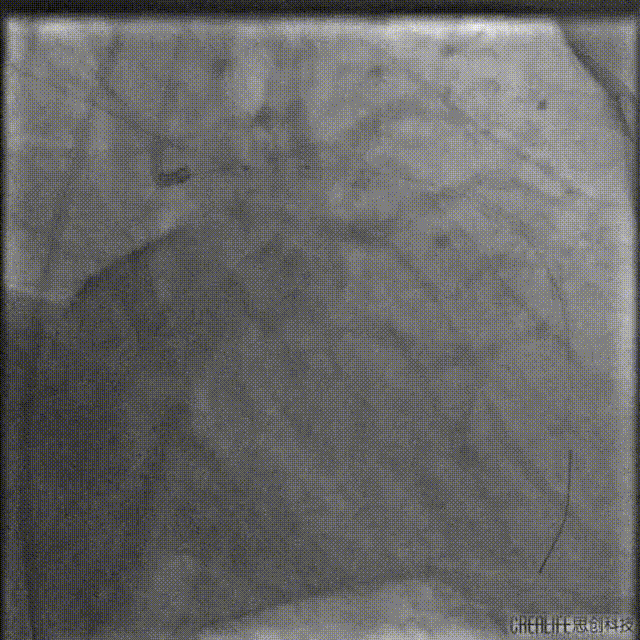

最终造影结果

复查造影未见明显狭窄,TIMI血流3级。

由远及近串联植入2.5*36mm、2.75*36mm、3.5*29mm支架三枚。

支架释放后造影,中段支架膨胀欠佳。

IVUS查看见支架远端局部血肿,遂远段植入2.25*29mm支架,并送入2.5*15mm球囊后扩,并用4.0*12mm球囊后扩近段支架。